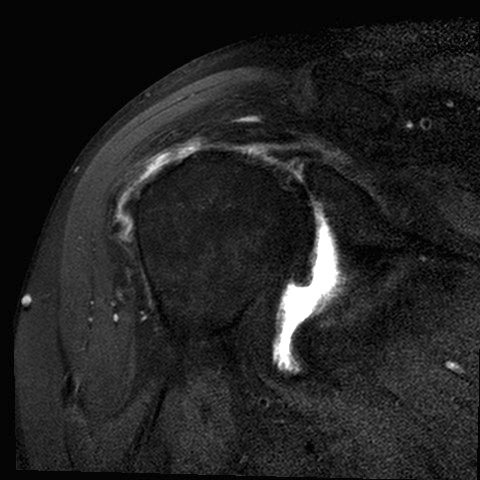

MRI

Rotator cuff tears

MRI with massive supraspinatus tear, subscapularis tear, and large Hill Sachs lesion

MRI with supraspinatus tear, Hill Sachs lesion and significant glenoid bony deficiency